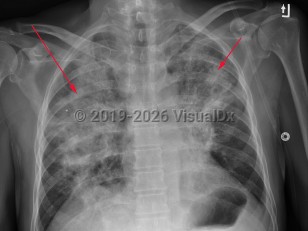

Fever, Cough, 50-59 year old Female

COVID-19